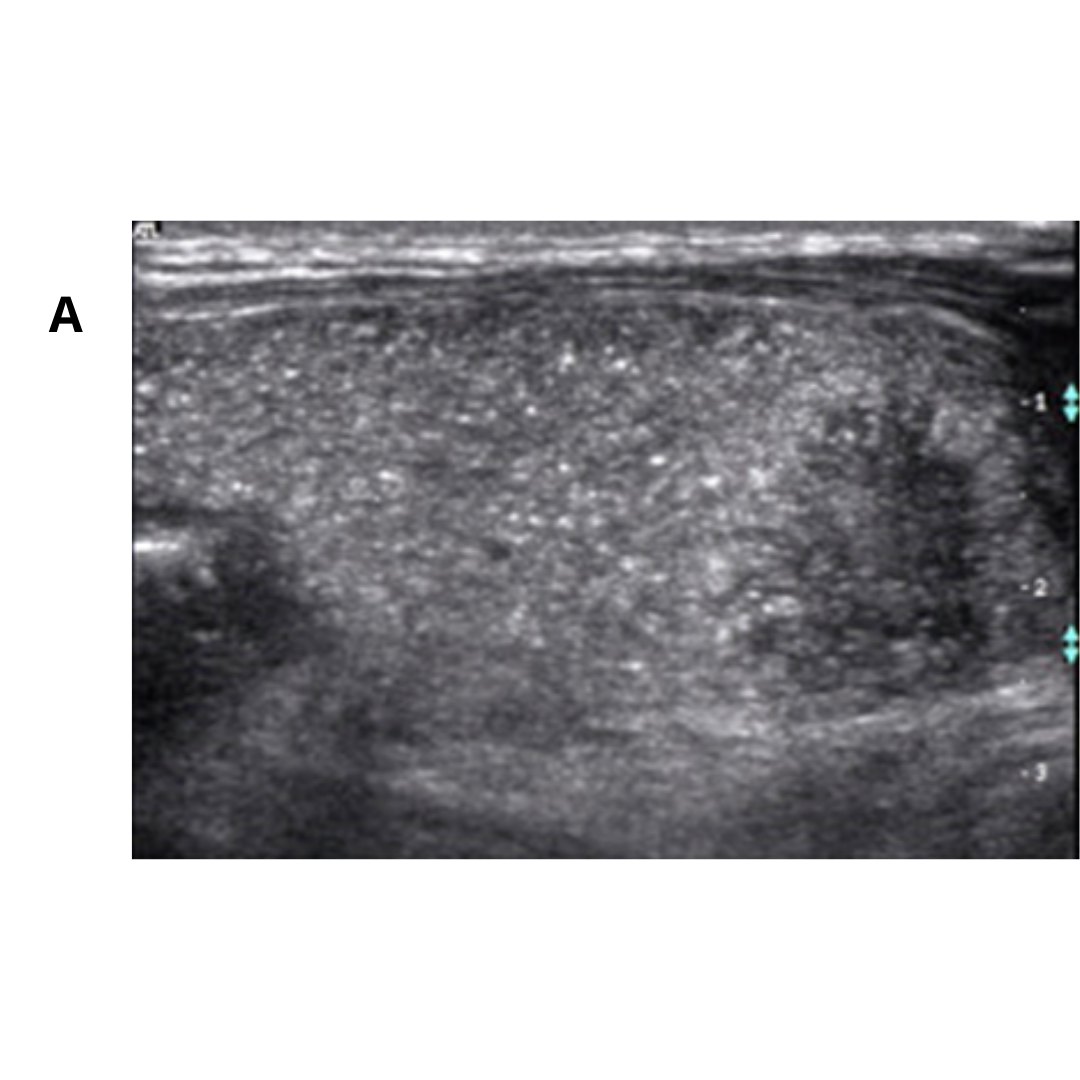

Según diferentes estudios (3,5,6,9), el carcinoma papilar esclerosante difuso, a nivel ecográfico, la glándula tiroides se visualizará aumentada de tamaño, hiperecogénica, heterogénea, con imágenes puntiformes dispersas correspondientes a MCC, lo que se puede confundir en principio con tiroiditis. A este patrón, de imágenes puntiformes distribuidas en el parénquima se denomina como “tormenta de nieve”. Puede o no existir masa asociada, la cual se presentará como un nódulo sólido, hipoecogénico, de bordes mal delimitados y abundantes MCC que sugieren una invasión en curso.

Fig3. (A) Numerosas microcalcificaciones en todo el lóbulo derecho como una “tormenta de nieve” sin nódulos en la sección longitudinal de la tiroides. (B) Patrón en “tormenta de nieve” en el lóbulo derecho con un nódulo hipoecoico de borde mal delimitado en el corte longitudinal de la tiroides (8).